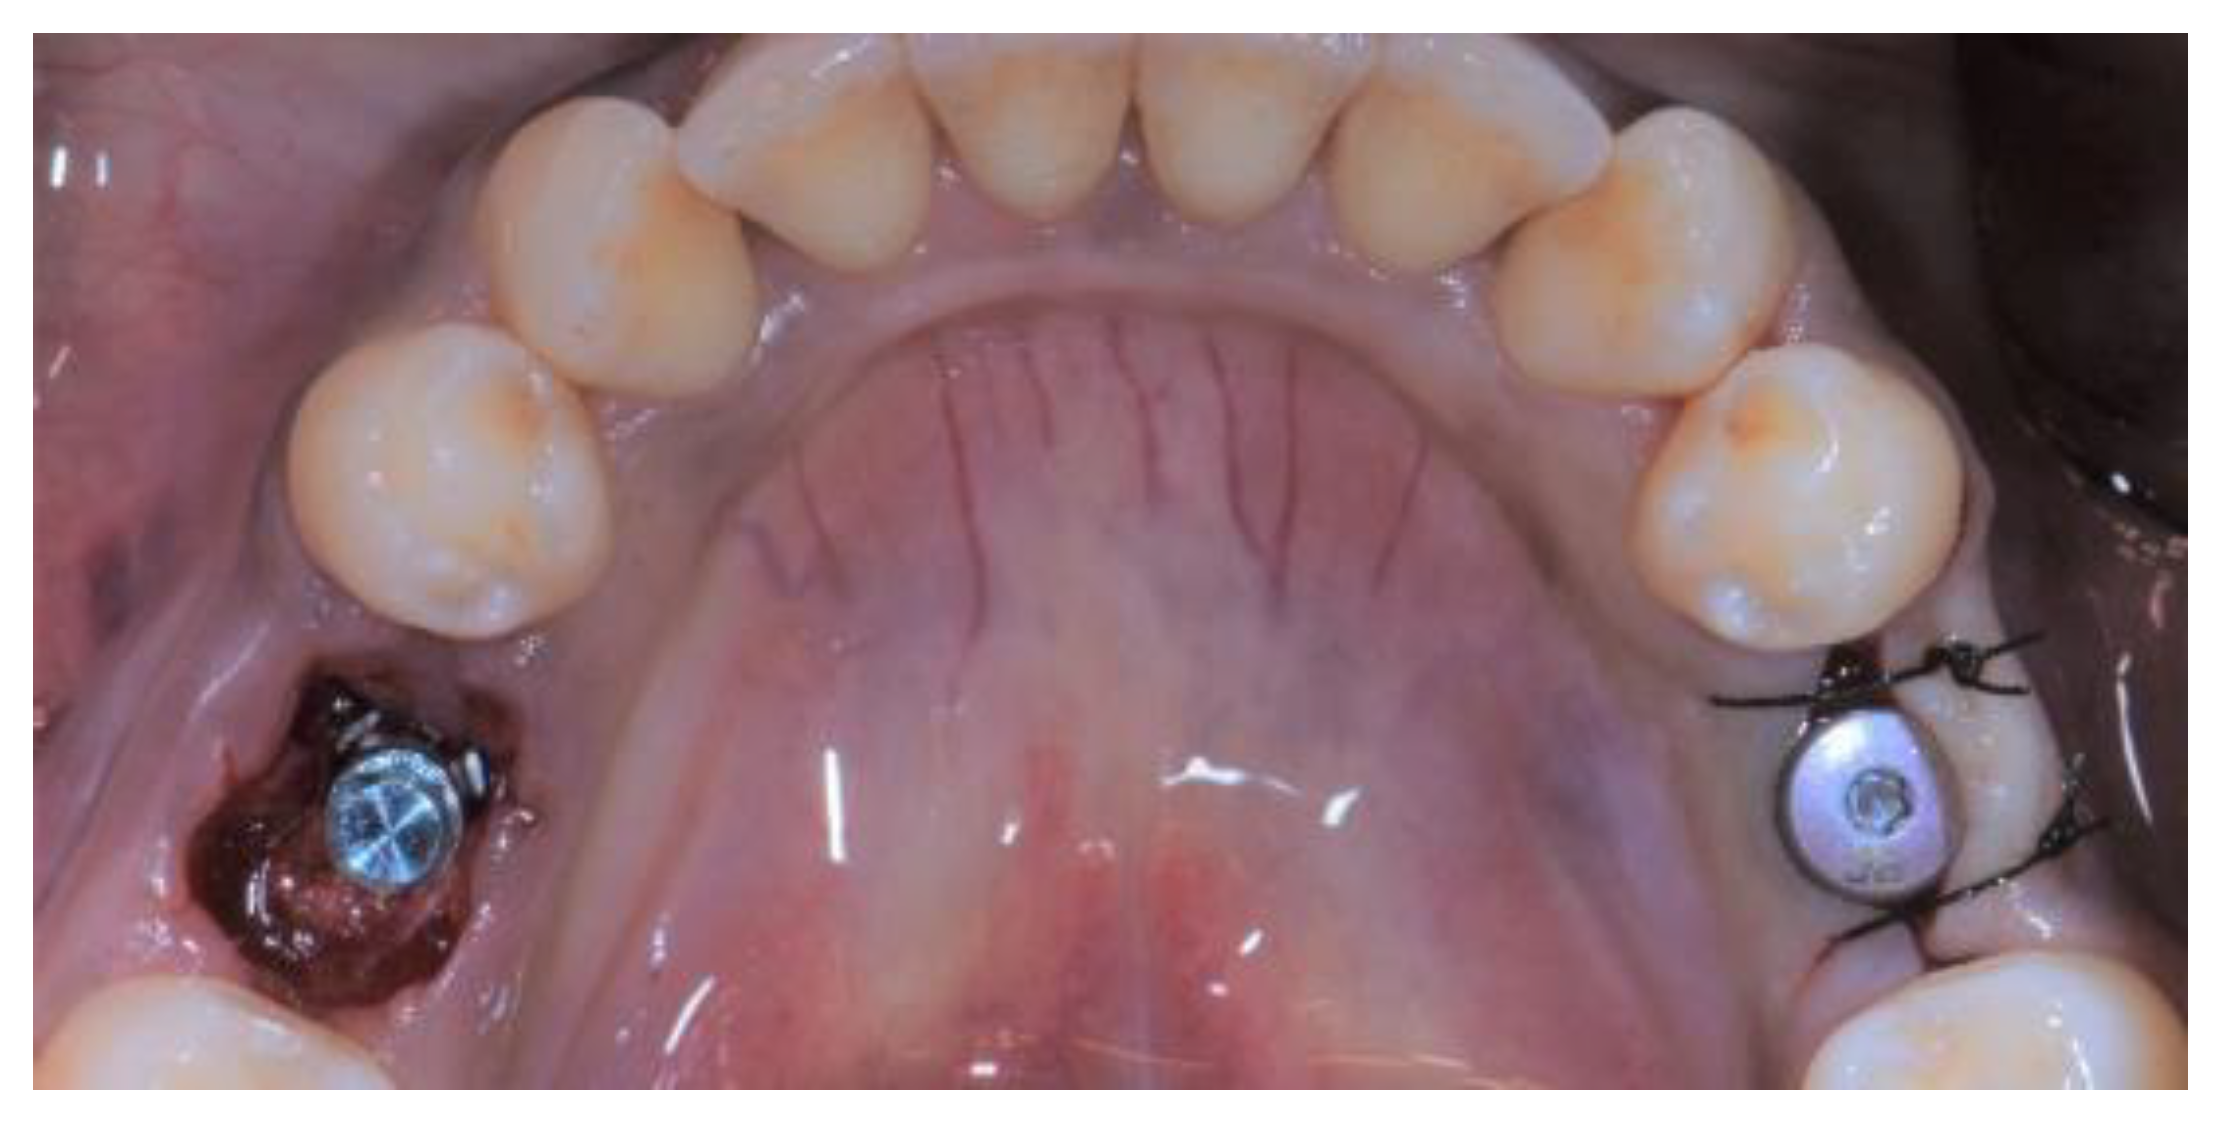

2.3. Treatment Procedure

2.5. Individual Cases Description

- Case 1:

- Case 2:

- Case 3:

- Case 4:

- Case 5: